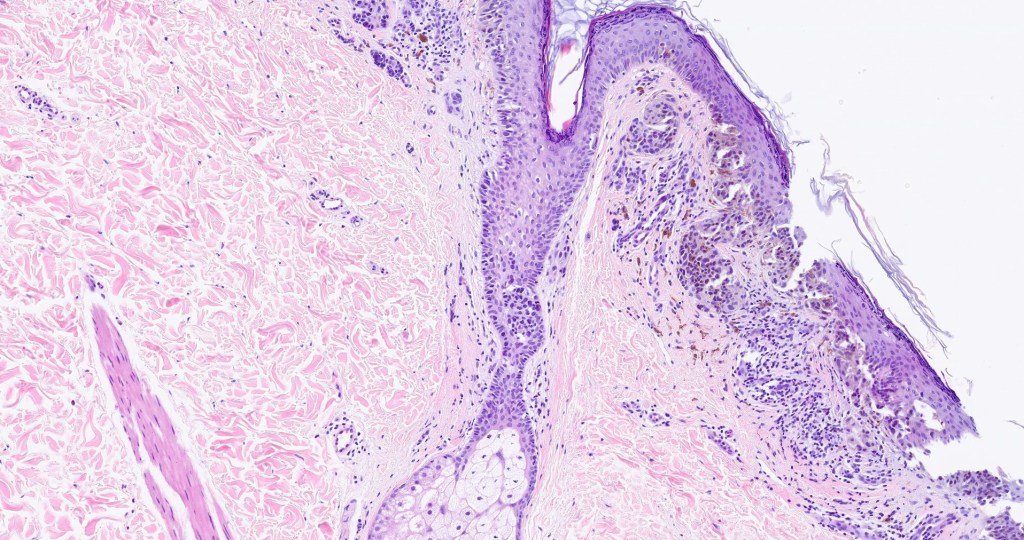

Histological features

•Junctional/compound

•Large dyscohesive nests with retraction artifact, not restricted to the tips of the epidermal ridges

•Heavy pigmentation (sometimes gray/green)

•Bridging common, often over multiple rete ridges

•Variable atypia (can be marked)

•Central pagetoid spread

•Superficial dermal atypia

•Junctional mitoses sometimes present, dermal mitoses+/-, can be multiple but never atypical

•Dermal fibrosis (sometimes lamellar)